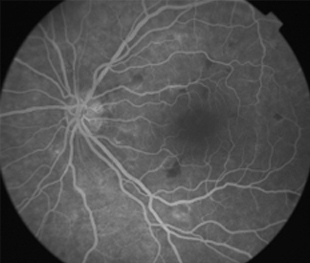

Angiografía OD

IDX

Retinopatía de Purtcher Secundaria a Embolismo Graso después de Liposucción

- Angiografía: teñido arterial, escape capilar, más tardíamente, no perfusion arteriolar y venular con teñido de las paredes vasculares y dilatación venosa.